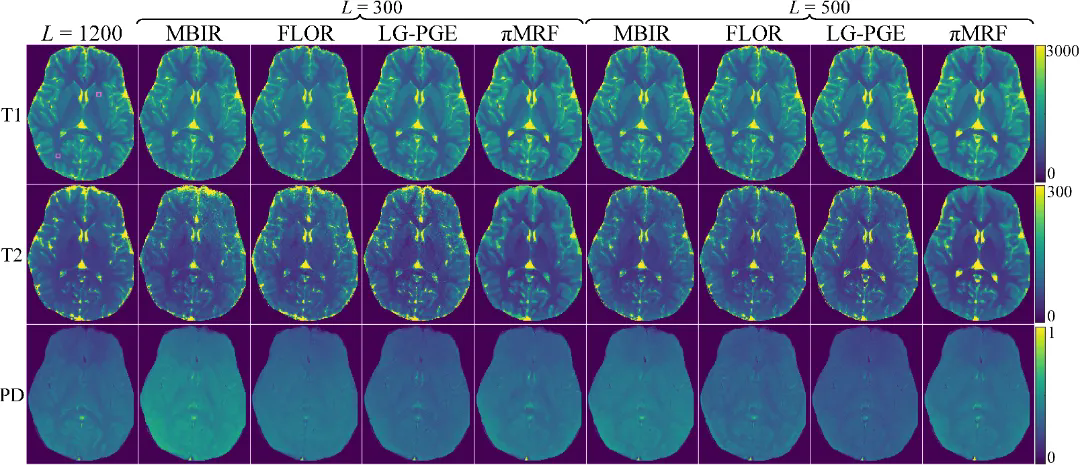

在数字仿真、水模仿体以及在体人脑实验中,πMRF在极端欠采样条件下均表现出更高的定量准确性与空间一致性,能够稳定恢复T1、T2和PD参数分布,并在组织边界及病灶区域保持更可靠的细节表达,整体性能显著优于现有对比方法。上述结果表明,该研究有效缓解了 MRF 在极端欠采样条件下面临的不适定逆问题,展示了“物理模型与陆续在神经表示深度融合”在复杂医学成像反演任务中的应用潜力。

图5:在体人脑实验结果